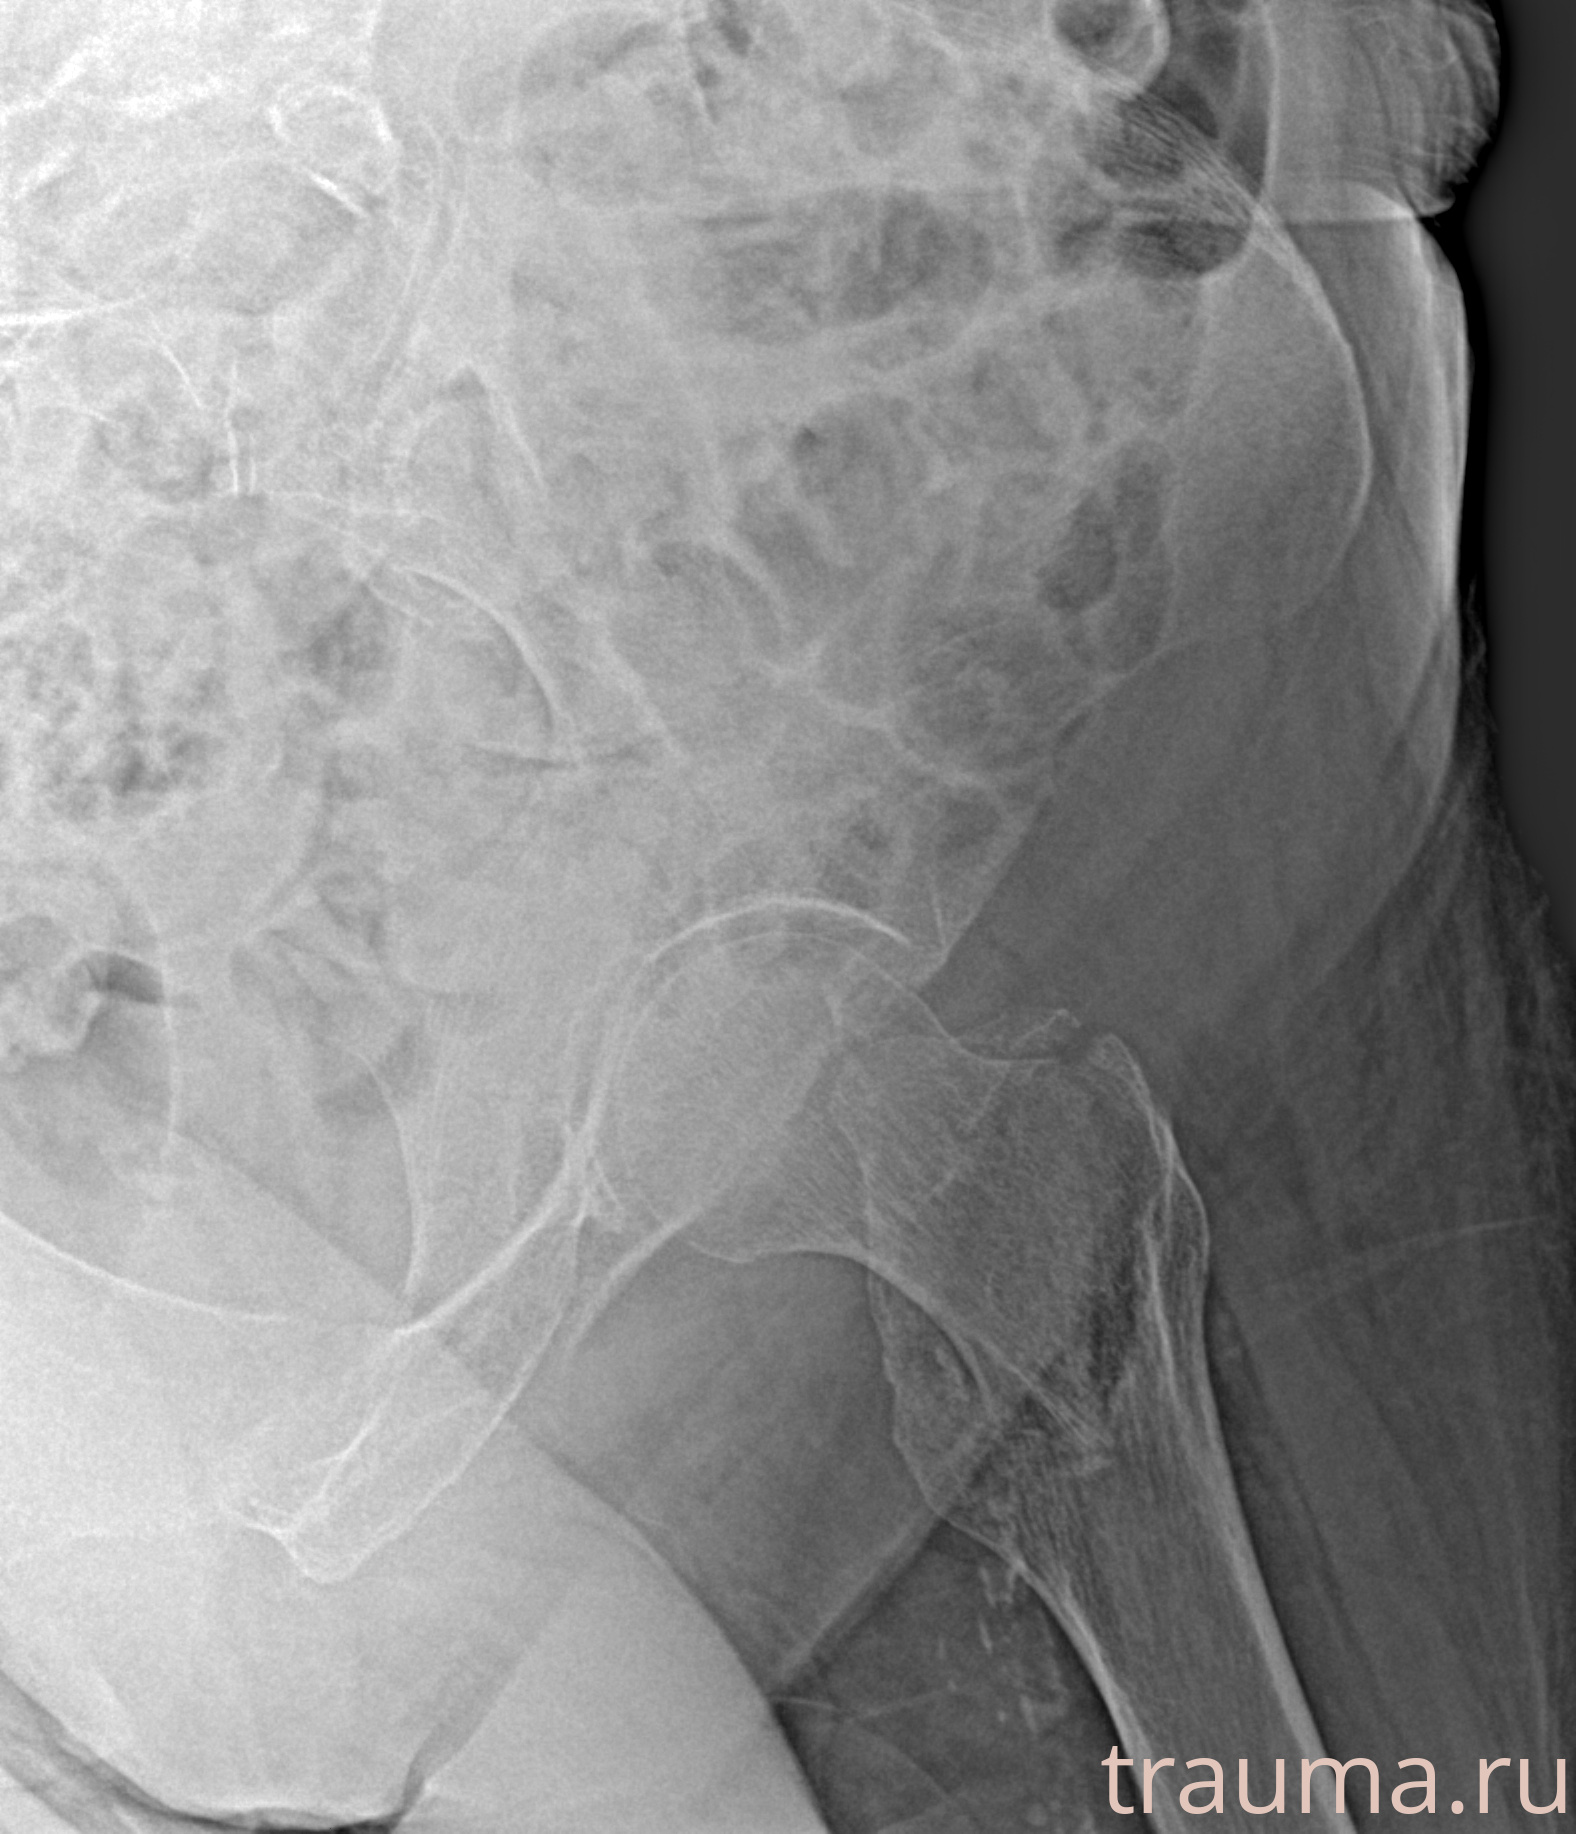

Рентгенограммы

Рентген на дому: по вашему адресу приезжает врач-рентгенолог, травматолог-ортопед с мобильным рентгеновским аппаратом, проводит диагностику травмы или заболевания, делает необходимые рентгенограммы, дает рекомендации по дальнейшему лечению. Получить качественные снимки в домашних условиях возможно благодаря уникальной методике, разработанной МосРентген Центром для института  Склифосовского